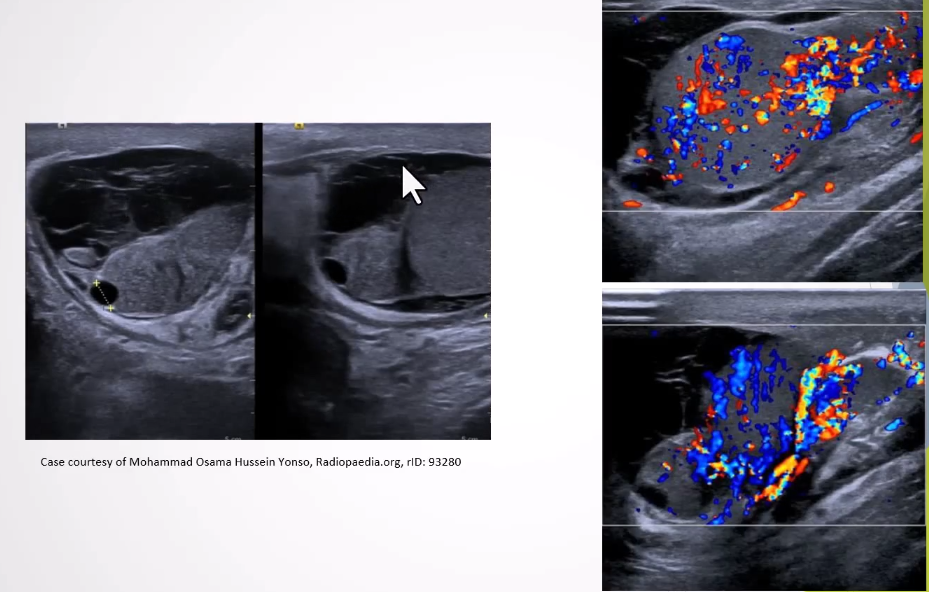

Cryptorchidism: Absence of testis in scrotal sac, due to undescended or ectopic testis.

Causes: Premature birth, IUGR, maternal lifestyle during pregnancy (smoking, alcohol).

Clinical presentation: one testis or both missing from scrotal sac

Ultrasound Appearance:

Lack of testis in scrotal sac; undescended testis appears homogenous and hypoechoic.